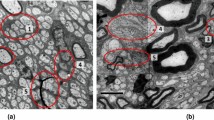

A STRETCH of nerve fibre which has been cut off from its cell body degenerates and disappears. There must, therefore, be some influence emanating from the cell body and nucleus which normally maintains the integrity of the axon. Two facts which throw light on the nature of this influence are that (1) during degeneration the isolated portion contracts and forms folds and spirals; (2) the central portion swells as if under the influence of a turgor pressure.